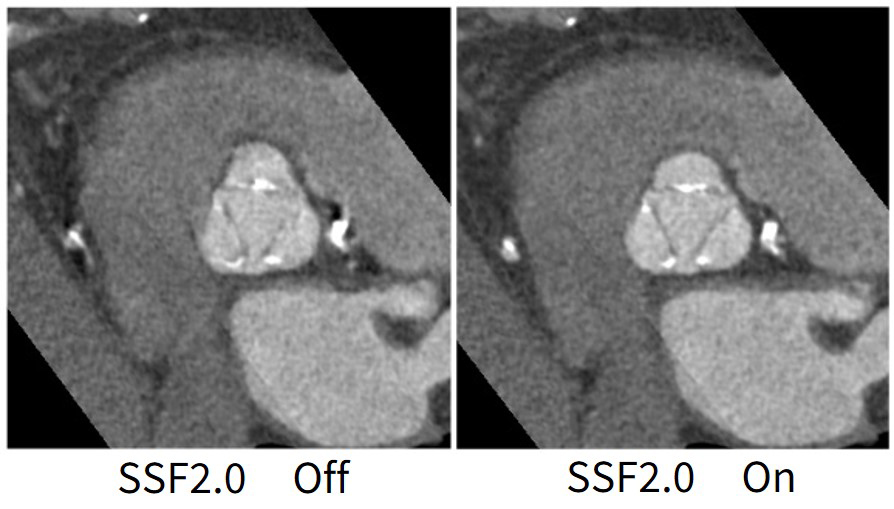

SSFではモーションアーチファクトにより評価困難だった症例も、SSF2.0によりモーションアーチファクトは大きく低減し、冠動脈の評価ができたことは好印象だった。またSSF2.0では冠動脈だけでなく心臓全体のモーションアーチファクトが低減されるため、弁膜症の術前検査やSHDの評価に役立つことを期待している。 (図8)

Maxima_AichiHeart08.jpg

図8. 大動脈弁評価(HR:61bpm, 25%再構成)